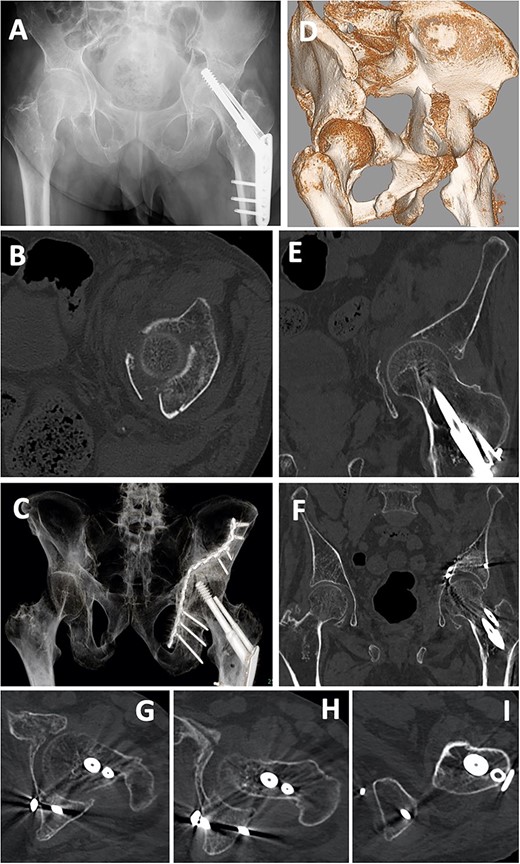

A 55-year-old man was involved in a motorcycle accident and taken to a nearby hospital. Diagnostic imaging showed a left acetabular fracture (Fig. 6A, C, D, F–J; both column fractures according to the AO classification). He was transferred to our hospital, and 12 days after the injury, open reduction and internal fixation were performed using a low-profile pelvic plate system (DePuySynthes Trauma, West Chester, PA, USA). The patient was placed in the supine position, and the classical ilioinguinal approach was used. The skin was cut from the pubic joint to the iliac crest, the abdominal muscles were released, and the retroperitoneal area and the fracture area were reached. Dislocation of the pelvic brim was reduced with a reduction clamp and fixed by a screw. After the internal obturator muscle was retracted, the quadrilateral fragment was reduced, a bent 12-hole, one-third plate was placed at the quadrilateral surface, and a screw was inserted from the posterior column to the ilium using the sleeve guide technique (Fig. 6K–O). In addition, two reconstruction plates were used for fixation from the anterior to the posterior ilium and from the pubis to the ilium (Fig. 6B, E). Six weeks after the operation, partial weight-bearing was started. After 3 months, the patient walked with a stick. After 1 year, he reported no hip or pelvic pain, and he walked without a gait abnormality.

Case 1 images: (A) pre-operative X-ray, (B) post-operative X-ray, (C) pre-operative 3D-CT (anterior), (D) pre-operative 3D-CT (posterior), (E) post-operative 3D-CT, (F–J) pre-operative axial CT images, (K–O) post-operative axial CT.